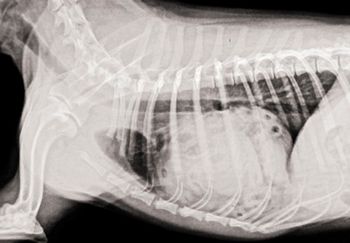

A hernia repair leads to this unusual radiographic finding.

The goals of this lecture are to provide you with techniques of radiography and radiology of the dog and cat thorax

The most important question to ask yourself is: Is the lung too opaque or too lucent?